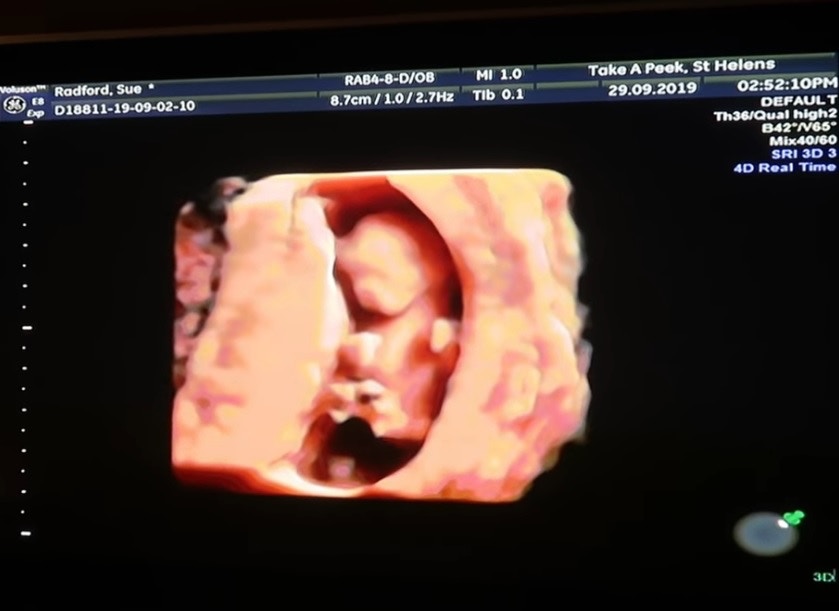

▼之前Sue有「封肚」的想法,Noel還到醫院接受結紮。但他們想繼續生小孩,Noel就去「解結」了。現在Sue懷上第22個小孩,預產期是明年4月。她特別透過YouTube分享了超聲波照片。

▼這位媽媽第22次懷孕啦。